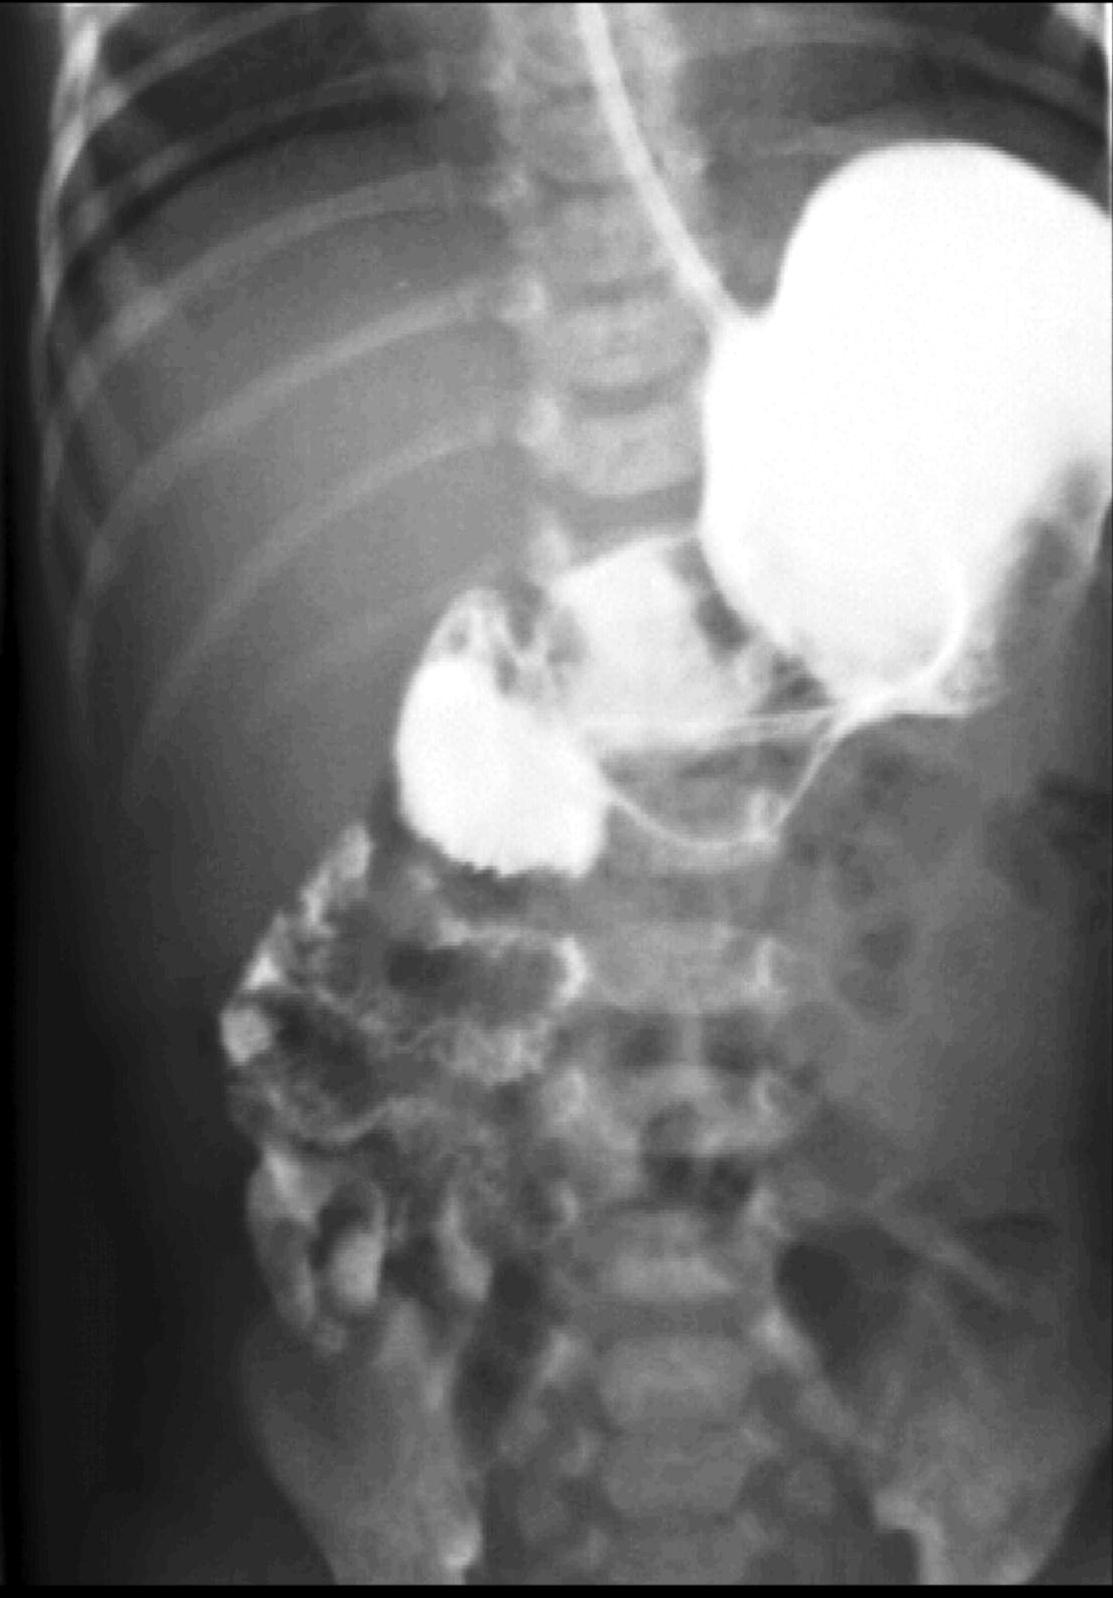

During X-ray examination the contrast material does not progress to the jejunal loops or it shows a “corkscrew” sign on the right side of the vertebrae as it piles up in the twisted intestinal loops.

Image

15. Contrast material empties the stomach slowly, small intestines are found on the right side of the abdomen. Malrotation-volvulus.